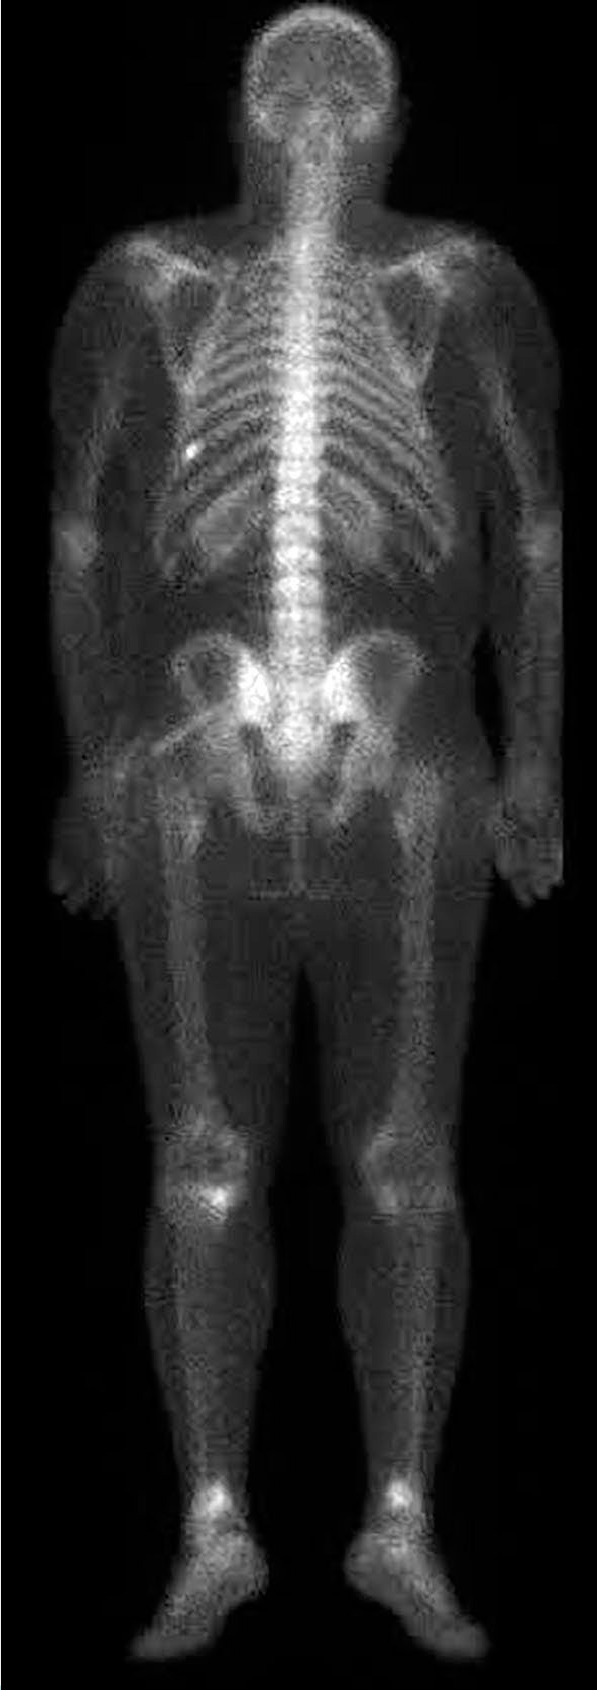

Intraosseous lipomas (IOLs) are rare benign bone tumors which can closely mimic malignancy on imaging, leading to diagnostic challenges. A 34-year-old male patient was admitted with persistent knee pain which was initially suspected to be metastatic bone disease. The patient reported activity-related pain relieved by rest. Physical examination revealed mild tenderness without swelling or restricted motion. Laboratory findings, including serum calcium and inflammatory markers, were normal. Magnetic resonance imaging (MRI) showed hyperintense lesions in the tibial and femoral metaphyses with surrounding bone marrow edema, raising suspicion of malignancy. Bone scintigraphy revealed increased radionuclide uptake in the tibial tuberosity, iliac crest, and the ninth rib, further mimicking metastatic disease. A biopsy of the tibial lesion confirmed mature adipocytes without necrosis or atypia, diagnosing IOLs. The patient was managed conservatively with non-steroidal anti-inflammatory drugs and physiotherapy. At three months, symptoms resolved completely, with no recurrence or new complaints. Follow-up MRI confirmed lesion stability. In conclusion, this case highlights the diagnostic complexity of IOLs and emphasizes the need for multimodal imaging and histopathological confirmation to differentiate benign lesions from malignancies. Including IOLs in the differential diagnosis of unexplained bone pain can prevent unnecessary invasive procedures and mistreatment.